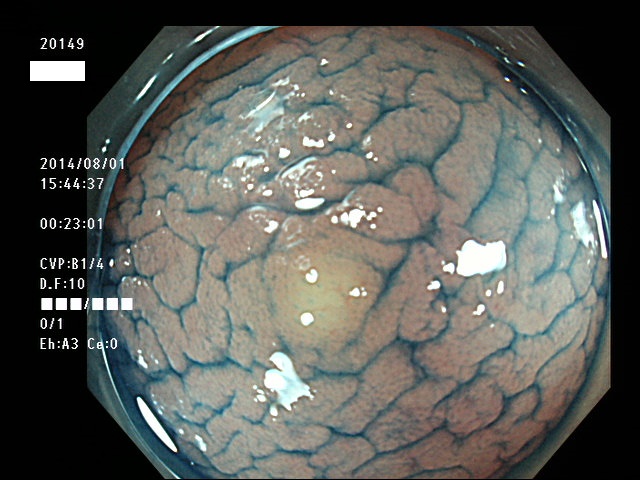

微小カルチノイドの診断

直腸の微小カルチノイドの診断は最も難しい問題です

微小とはいえ、カルチノイドは悪性であり、肛門に近い場所に好発するために、見落とすと数年後には「人工肛門」になる危険があります

進行したカルチノイドの診断は容易なのですが、カルチノイドは「粘膜下腫瘍」と言いまして、は表面が正常粘膜で被われているために微小ですと「単なる過形成結節」「単なる炎症性の隆起」と区別がつかないのです

下記の写真は全て、当院で診断された微小カルチノイド(悪性)ですが、いかに診断が困難かお分かりいただけるでしょう。このような微小病変でさえも見落とせば人工肛門の危険が潜んでいる訳です。